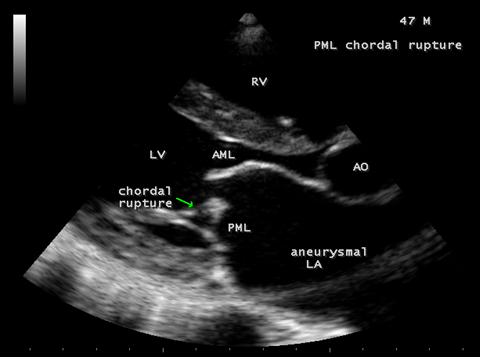

Case 2. PML (posterior mitral leaflet) prolapse causing severe mitral regurgitation with aneurysmal LA (left atrium) as shown in Figures 3 to 8 due to PML chordal rupture of rheumatic etiology in a 47- year old male. Patient was advised lifelong penicillin prophylaxis and MVR (mitral valve replacement).

Figure 4. Parasternal long axis view showing the PML (posterior mitral leaflet) chordal rupture of rheumatic etiology in a 47-year-old male. Both AML (anterior mitral leaflet) and PML (posterior mitral leaflet) of mitral valve are thick and calcified due to rheumatic etiology.